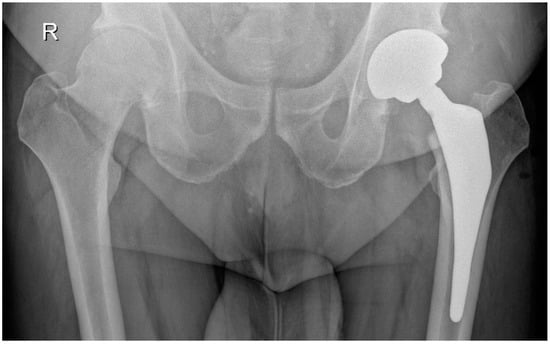

Acetabular reaming and cup placement were performed using offset reamers and cup insertion handles. After a capsular release performed with electrocautery, the femur was prepared using a single custom-made rasp. The custom-made femoral stem, with 2/3 hydroxyapatite coverage and ceramic femoral heads, was implanted, and hip stability was checked post-reduction. Figure 4 and Figure 5 show a patient with coxarthritis of the left hip and his postoperative X-ray.

Figure 5. Postoperative X-ray of the same patient after a custom-made THA on the left side.